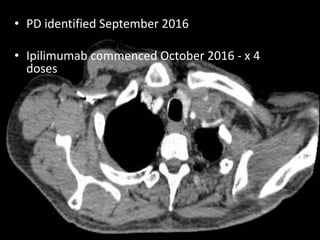

• PD identified September 2016

• Ipilimumab commenced October 2016 - x 4

doses

• 29th December 2016

• Presents to ED- lethargy, fever, SOB at rest,

anorexia

• No coryzal symptoms, no chest pain, no

PND, no ankle swelling

• Exercise tolerance < 30m